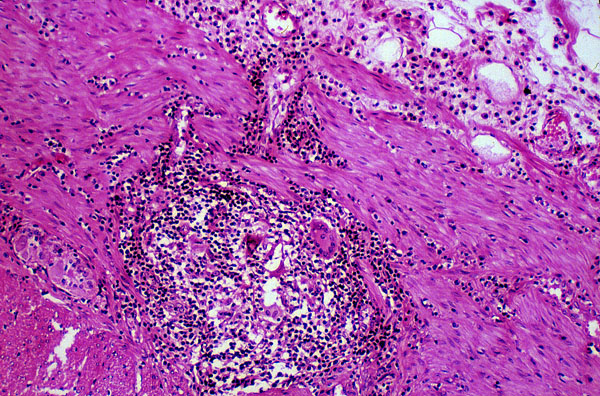

Crohn disease, histology

This photograph shows the muscle layer of the large intestine which contains a granuloma with multinucleated giant cells.